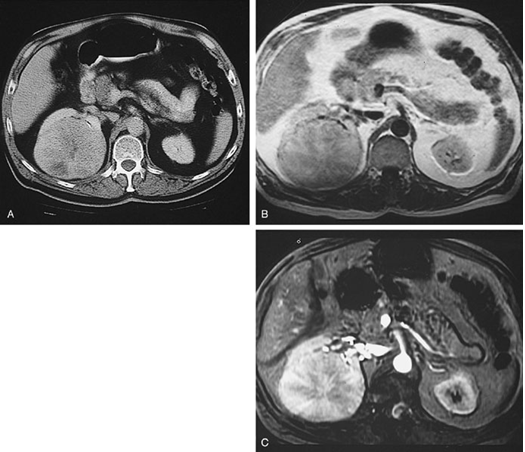

What features of this CT allow the diagnosis of oncocytoma to be made?

Large rounded mass within the kidney with central scar